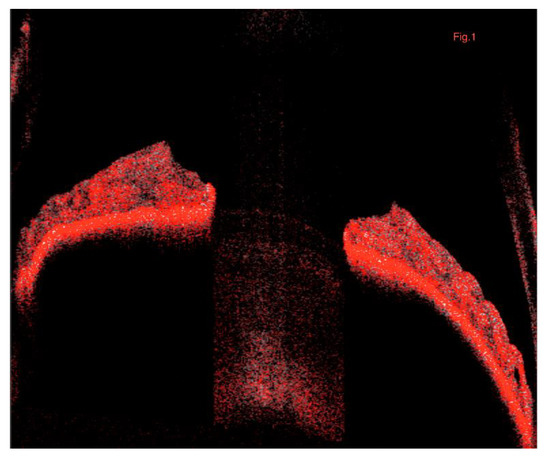

2.3. Imaging

2.4. Image Processing